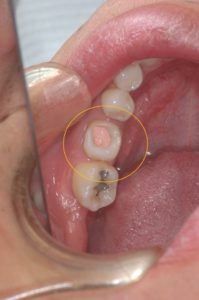

下写真の歯(オレンジ〇)は歯根破折しており抜歯になります。その代わりに親知らず(青〇)を移植する計画としました。